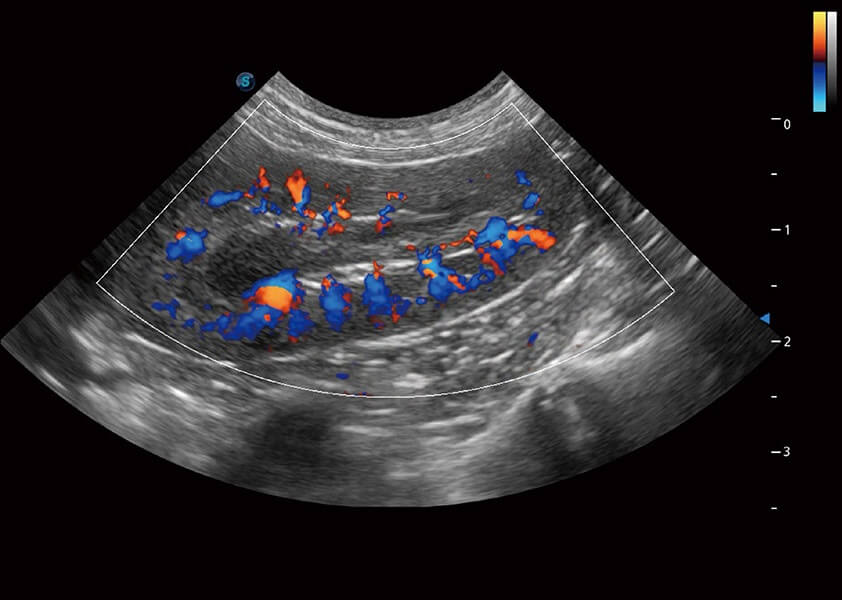

4T血流成像 微察秋毫

融合不同血流成像技术的优势,即可以提升血流成束性,同时可提高血流的视觉敏感性。

PDI 能量多普勒血流

提供高灵敏度和空间分辦率的血流图像,获得更加真实和丰富的诊断信息。

SR Flow 高分辨率血流成像

能够清晰显示细小、低速血流图像,获取传统彩色多普勒技术难以得到的细节和信息。

Micro F 显微血流成像

通过创新的Matrix E自适应滤波器和超长时间域算法,极大提升超低速微细血流的检出能力,同时更精准地滤除软组织和噪声信号,为兽用医生提供以往无法通过常规血流获得的疾病诊断信息。

Bright Flow 立体血流成像

在传统二维血流成像的基础上,呈现血流的立体感,具有动感的生命力之美。精确区分不同血管的空间关系,提高了血流的视觉敏感性。

(犬)四腔心血流

(犬)肾脏血流